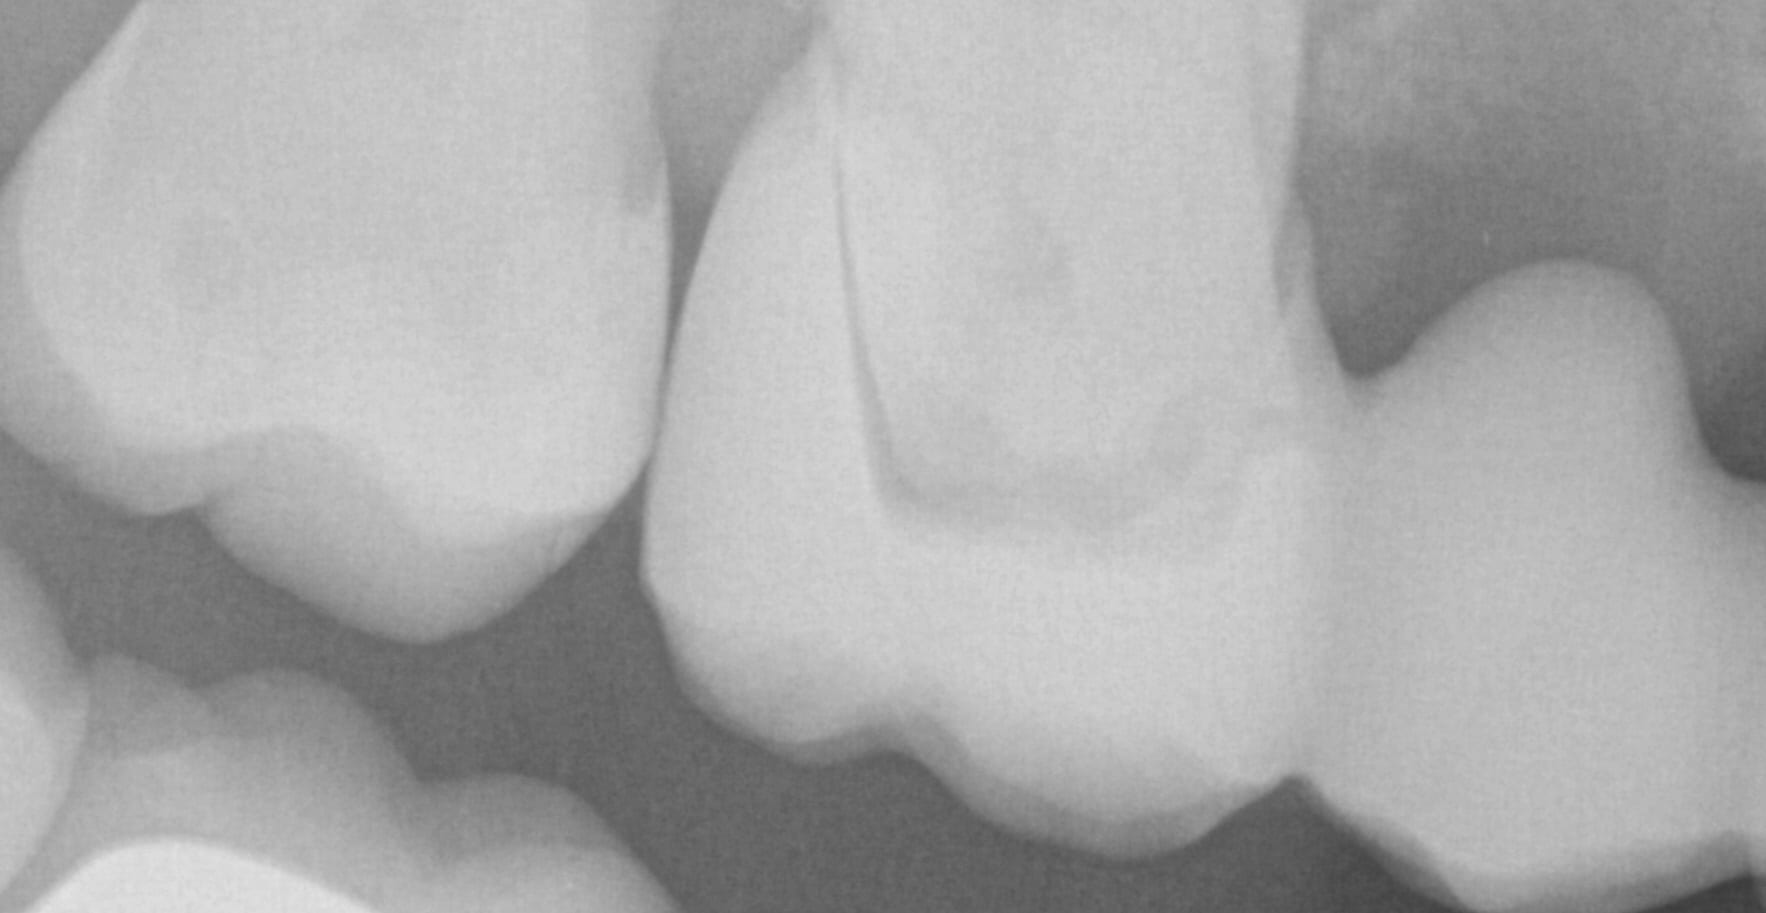

You can scam the opposing (here the upper hybrid was being repaired as the left central incisor had fallen off), scan the denture in place of the appropriate arch, and then you can take the buccal bite.